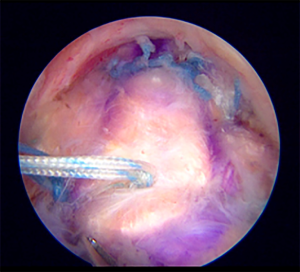

Graft harvesting and preparation

An ipsilateral fascia lata graft was harvested and prepared as a double-folded, 2-layered graft. To allow space for suture and knot tying, a 5-mm length was added to the final size of the graft. It is preferred to reinforce the graft construct by inserting a single layer of polypropylene mesh (Prolene Mesh®; Ethicon Inc, NJ, USA) into the folded fascia lata graft in a sandwich fashion (Figure 3). A running stitch no. 2-0 polyester suture (Ethibond®) was used to seal the graft margin. At least 6-mm-thick graft was obtained during the final graft preparation. The bursal side of the graft was marked to ease the intraarticular orientation of the graft position. A pair of heavy suture was added at the humeral side of the graft to facilitate the graft shuttling and tensioning. A saline-soaked gauze was used to cover the graft while waiting for shuttling. A routine local anesthetic injection was given to the donor site after a formal closure.